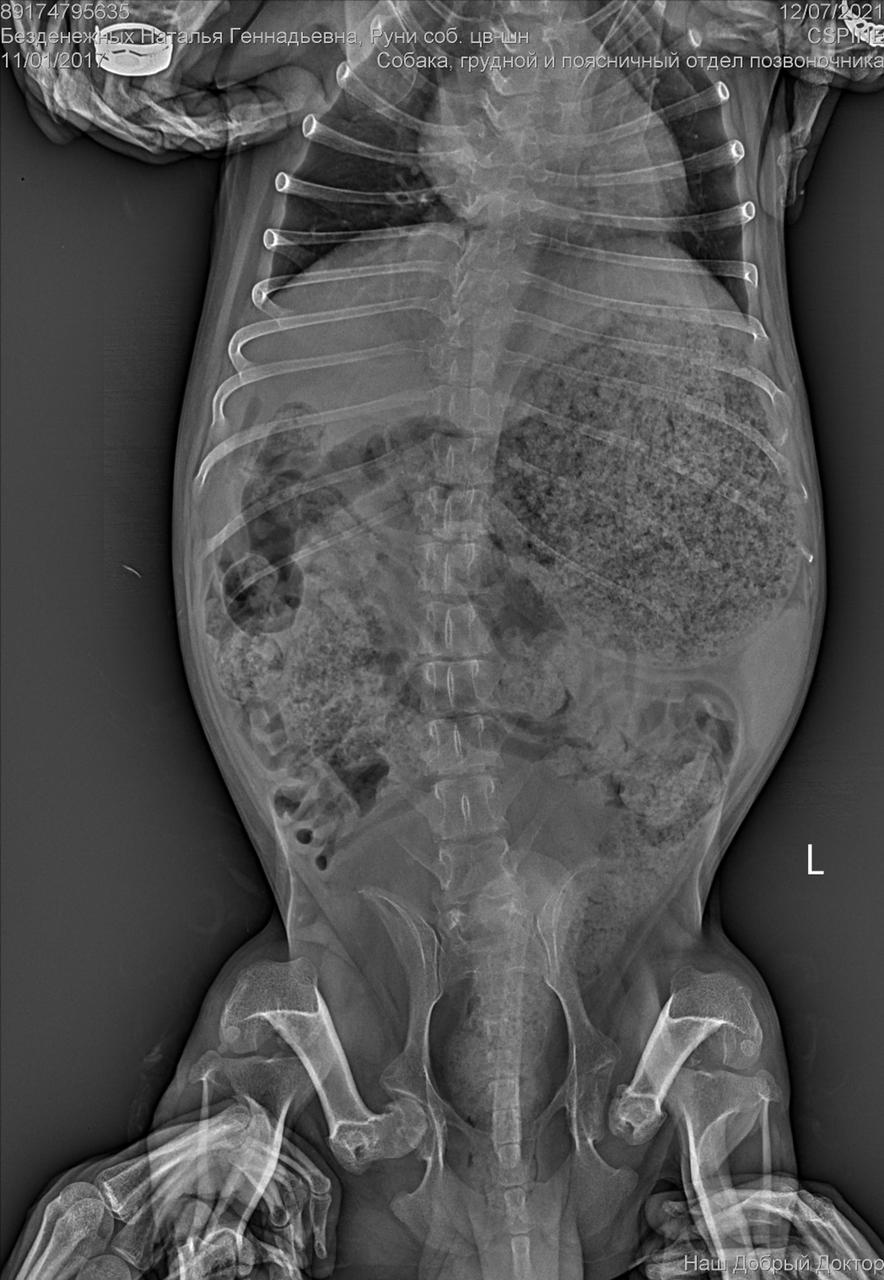

Сегодня утром под окнами дома, по адресу Дмитриева 1, был найден такой замечательный парень, задние лапы похоже перебиты, оставить умирать его я не смогла. Кто-то безжалостно выбросил маленького на улицу и оставил умирать, без еды и питья. Забрала временно к себе, сегодня повезем к ветеринару, оставить у себя возможности нет(моя собака в стрессе) , может кто то его ищет или хочет взять себе, давайте найдём пёсику дом (мама и папу)

С собакой сегодня поедут в клинику. Передержать и полечить смогут. Попросила в клинике посмотреть клеймо и посканировать ип.

ПОнадобится наша помощь с оплатой лечения и поиском дома.